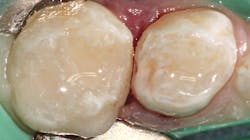

In this case, a W3 ivory rubber dam clamp is placed on tooth A to be restored with an intracoronal restoration. Adjacent tooth B will be restored with a prefabricated pediatric zirconia crown (NuSmile; figure 1). A Hedy rubber dam with a slot style is placed extending from tooth A to the mesial of tooth C.